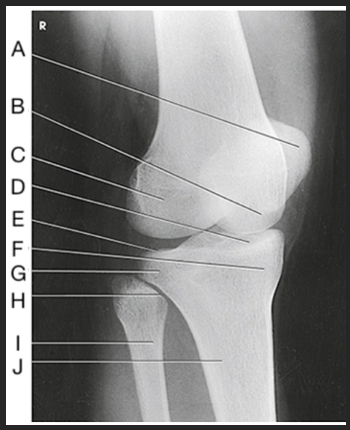

Name this projection.

AP oblique lateral rotation

What is demonstrated?

Medial aspect (distal femur, patella, medial tibial condyles, and fibula)

Label the image: A

femur

Label the image: B

patella

Label the image: C

medial femoral condyle

Label the image: D

lateral femoral condyle

Label the image: E

Lateral tibial plateau

Label the image: F

medial tibial plateau

Label the image: G

medial tibial condyle

Label the image: H

fibula

Label the image: I

tibia